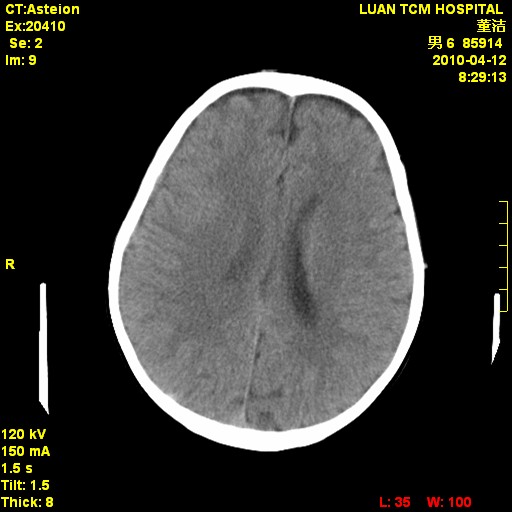

标题: PED3404:有结果,先猜猜这是啥病表现?男,12岁。 [打印本页]

标题: PED3404:有结果,先猜猜这是啥病表现?男,12岁。

右侧额顶部自颅板向内近似半圆高密度影,周围无明显水肿,考虑:脑外血肿?脑膜瘤?淋巴瘤?